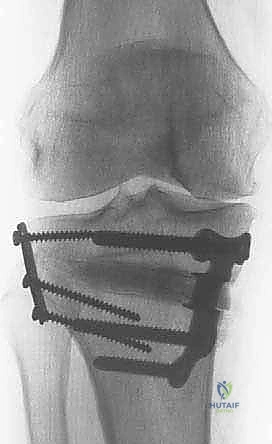

خطوات الجراحة: رحلة دقيقة داخل غرفة العمليات

تُجرى عملية قطع عظم الظنبوب القاصي تحت التخدير النصفي أو الكلي، وتستغرق عادة من ساعة إلى ساعتين. إليك التفاصيل الدقيقة لما يحدث داخل غرفة العمليات تحت إشراف الأستاذ الدكتور محمد هطيف:

3. إجراء القطع العظمي (The Osteotomy):

باستخدام أدوات دقيقة ومناشير جراحية متطورة، يتم عمل قطع غير مكتمل في عظمة الساق. هناك طريقتان رئيسيتان:

* الشق المفتوح (Opening Wedge): يتم فتح العظم من الداخل وإضافة طعم عظمي (صناعي أو طبيعي) لملء الفراغ وتعديل الزاوية. وهي الطريقة الأكثر شيوعاً حالياً.

* الشق المغلق (Closing Wedge): يتم إزالة إسفين (مثلث) صغير من العظم من الجهة الخارجية وإغلاق الفراغ.

4. تعديل المحور:

يتم فتح العظم تدريجياً وببطء شديد حتى الوصول إلى الزاوية التي تم حسابها في التخطيط الرقمي قبل الجراحة.